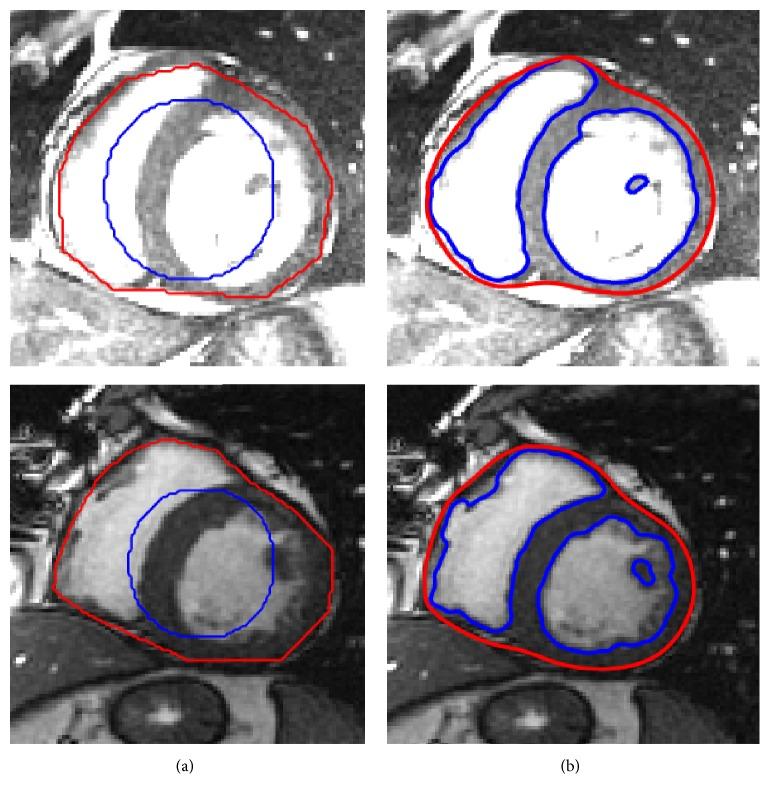

Segmentation of left and right ventricles plays a crucial role in quantitatively analyzing the global and regional information in the cardiac magnetic resonance imaging (MRI). In MRI, the intensity inhomogeneity and weak or blurred object boundaries are the problems, which makes it difficult for the intensity-based segmentation methods to properly delineate the regions of interests (ROI). In this paper, a hybrid signed pressure force function (SPF) is proposed, which yields both local and global image fitted differences in an additive fashion. A characteristic term is also introduced in the SPF function to restrict the contour within the ROI. The overlapping dice index and Hausdorff-Distance metrics have been used over cardiac datasets for quantitative validation. Using 2009 LV MICCAI validation dataset, the proposed method yields DSC values of 0.95 and 0.97 for endocardial and epicardial contours, respectively. Using 2012 RV MICCAI dataset, for the endocardial region, the proposed method yields DSC values of 0.97 and 0.90 and HD values of 8.51 and 7.67 for ED and ES, respectively. For the epicardial region, it yields DSC values of 0.92 and 0.91 and HD values of 6.47 and 9.34 for ED and ES, respectively. Results show its robustness in the segmentation application of the cardiac MRI.

左心室和右心室的分割在定量分析心脏磁共振成像(MRI)中的全局和局部信息方面起着至关重要的作用。在MRI中,强度不均匀性以及目标边界模糊或微弱是存在的问题,这使得基于强度的分割方法难以准确勾勒出感兴趣区域(ROI)。本文提出了一种混合符号压力力函数(SPF),它以相加的方式产生局部和全局图像拟合差异。在SPF函数中还引入了一个特征项,以将轮廓限制在ROI内。重叠骰子指数和豪斯多夫距离度量已用于心脏数据集进行定量验证。使用2009年左心室MICCAI验证数据集,所提出的方法对于心内膜和心外膜轮廓分别产生0.95和0.97的DSC值。使用2012年右心室MICCAI数据集,对于心内膜区域,所提出的方法对于舒张末期(ED)和收缩末期(ES)分别产生0.97和0.90的DSC值以及8.51和7.67的HD值。对于心外膜区域,对于ED和ES分别产生0.92和0.91的DSC值以及6.47和9.34的HD值。结果表明了其在心脏MRI分割应用中的鲁棒性。